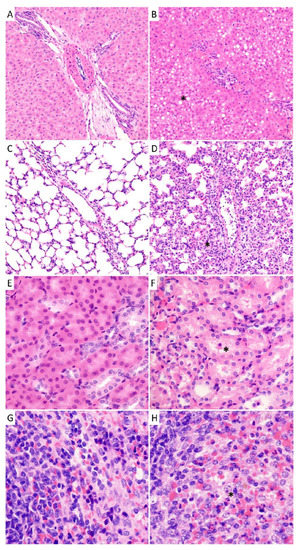

3.8. Pathology and Histopathological Analysis